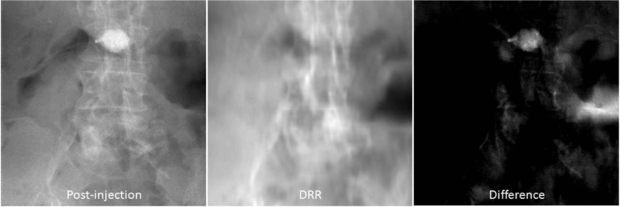

In the lumbar vertebroplasty case, a prior CT volume was used as a prior volume and registered to the post-injection CBCT x-ray projections using the method in section 2.2. Figure 10 shows example images of the post-injection CBCT projections, DRR computed from the registered prior CT and the resulting difference image. Since the prior CT was rigidly registered to the CBCT projections, there are intensity mismatches especially in the soft tissue and air regions. Also DRR looks blurred compared to the post-injection x-ray image due to the low spatial resolution of the CT data. However, the bone cement is clearly highlighted in the difference image. Similarity measures between the reconstructed VOCs and the ground truth as a function of different β values are computed and plotted in figure 11. Similar to the thoracic vertebroplasty case, there were only minor reconstruction quality variations between 20 and 66 projections although image quality degradation was relatively large when only 10 projections were used. Figure 12 shows example slice images of the VOC reconstruction computed from 20 projections with β = 107 (chosen from the similarity measures shown in figure 11) and merged with the pre-injection CBCT prior volume. Both the surgical change and the background patient anatomy are clearly visible and the extravasation can be detected in the final VOC reconstruction although it is very hard to see the injected bone cement in relation to the patient anatomy in the FBP reconstruction from the same 20 post-injection x-ray images.

Figure 10. Example projections (log-corrected). (Left) Post-injection x-ray image. (Middle) DRR computed from the registered CT prior volume. (Right) Difference image.